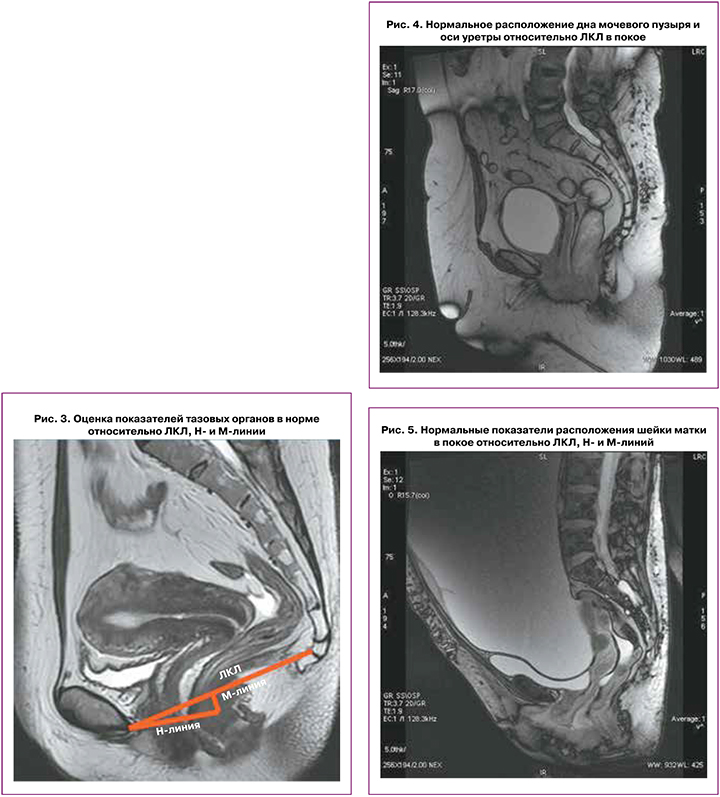

Показатели состояния тазовых органов оцениваются относительно ЛКЛ, соединяющей нижний край лобкового симфиза с последним копчиковым сочленением; линия Н – линия, соединяющая нижний край лонного симфиза с задней стенкой аноректального соединения – соответствует мочеполовой щели, сагиттальный ее размер не должен превышать 5 см; линия М – перпендикуляр, соединяющий линию Н с ЛКЛ – не должна превышать 2 см (рис. 3).

В покое дно мочевого пузыря расположено на 2 см выше ЛКЛ; при натуживании может смещаться на 8 мм ниже ЛКЛ; в покое и при натуживании ось уретры располагается вертикально, может незначительно смещаться при натуживании, просвет уретры не зияет (рис. 4).

В покое шейка матки расположена на 4 см выше ЛКЛ, при натуживании – на 8 мм выше ЛКЛ, при этом Ни М‑линии при натуживании удлиняются незначительно (рис. 5).